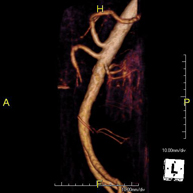

Prova diagnòstica no invasiva que consisteix en l'estudi de l'artèria aorta abdominal per obtenir imatges d'alta definició anatòmica mitjançant l'ús d'un camp electromagnètic i ones de ràdio (amb un emissor i un receptor). És indispensable l'ús de contrast intravenós paramagnètic (Gadolini). No obstant, no utilitza radiació ionitzant. La qualitat de les imatges permet realitzar reconstruccions en 2D i 3D. Està indicat en aquells pacients amb malaltia vascular (Aterosclerosi), per a l'estudi d'aneurismes, en estudis prequirúrgics de lesions adjacents a l'aorta abdominal com "mapa" vascular, etc. - Angio-RM Aorta ilíaca

Prova diagnòstica no invasiva que consisteix en l'estudi de l'artèria aorta abdominal per obtenir imatges d'alta definició anatòmica mitjançant l'ús d'un camp electromagnètic i ones de ràdio (amb un emissor i un receptor). És indispensable l'ús de contrast intravenós paramagnètic (Gadolini). No obstant, no utilitza radiació ionitzant. La qualitat de les imatges permet realitzar reconstruccions en 2D i 3D. Aquesta prova està especialment indicada com estudi prequirúrgic (mapa vascular) abans d'intervencions percutànies o quirúrgiques d'aorta abdominal, per a l'estudi complementari en pacients amb isquèmia de membres inferiors, etc. - Angio-RM d'Artèries renals